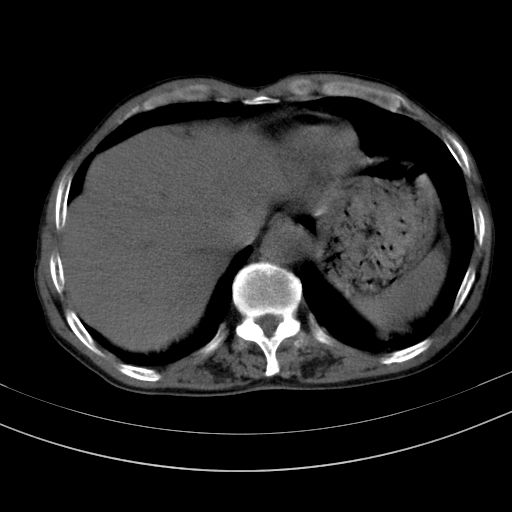

以下是引用37度在2010-1-9 14:37:00的发言:[br]1.双肾囊肿,左肾积水结石,.胆总管轻度扩张;[br]2.病灶在腹膜外,考虑纤维瘤。

以下是引用dyqct在2010-1-9 17:56:00的发言:[br]考虑:1.双肾囊肿,左肾积水结石、旋转不良。[br] 2.右侧腹直肌血肿或纤维瘤。[br]肠道准备不好。做个增强。